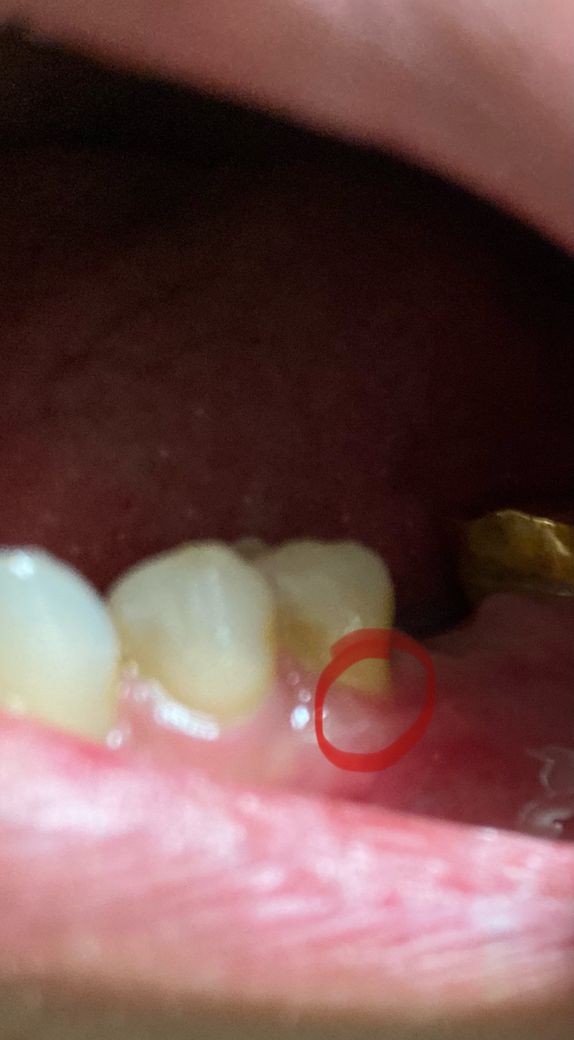

잇몸절개하고 뼈이식했는데 옆치아 잇몸이 살짝 내려가서 뿌리가 보이는것같아요. 손톱으로 살짝 긁어보면 법랑질 느낌이랑 좀 달라요.

절개한 잇몸 꿰맬때 마감이 잘못된건 아닐까요?

잇몸을 열어서 수술을 하고 다시 봉합한다면 불가피하게 잇몸의 위치나 모양이 달라지고 퇴축이 발생하기도 합니다.

잇몸절개하고 뼈이식했는데 옆치아 잇몸이 살짝 내려가서 뿌리가 나타나는 경우에 수술 한지 얼마안되어 일시적으로 생긴 증상일 가능성이 높습니다. 대부분 시간이 지나면 좋아지며, 만약 시간이 지나도 회복이 되지 않는 경우에는 퇴축이기에 시리고 불편감이 있는 경우 치과 진료를 권합니다.